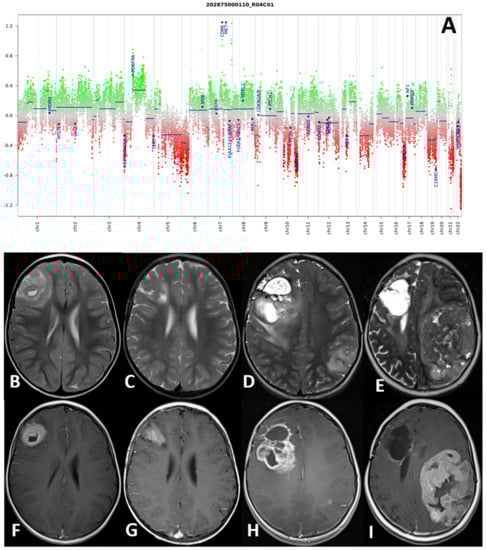

| 1 | 0 | RH | HGG | ETV6-NTRK3 | IHG (score 0.99) | IHG (score 0.99) | 5 | 47 | A |

| 1 | STR | AIEOP CNS Infants | N | Y | 5 | N | Y | Y (larotrectinib) | A | 47 |